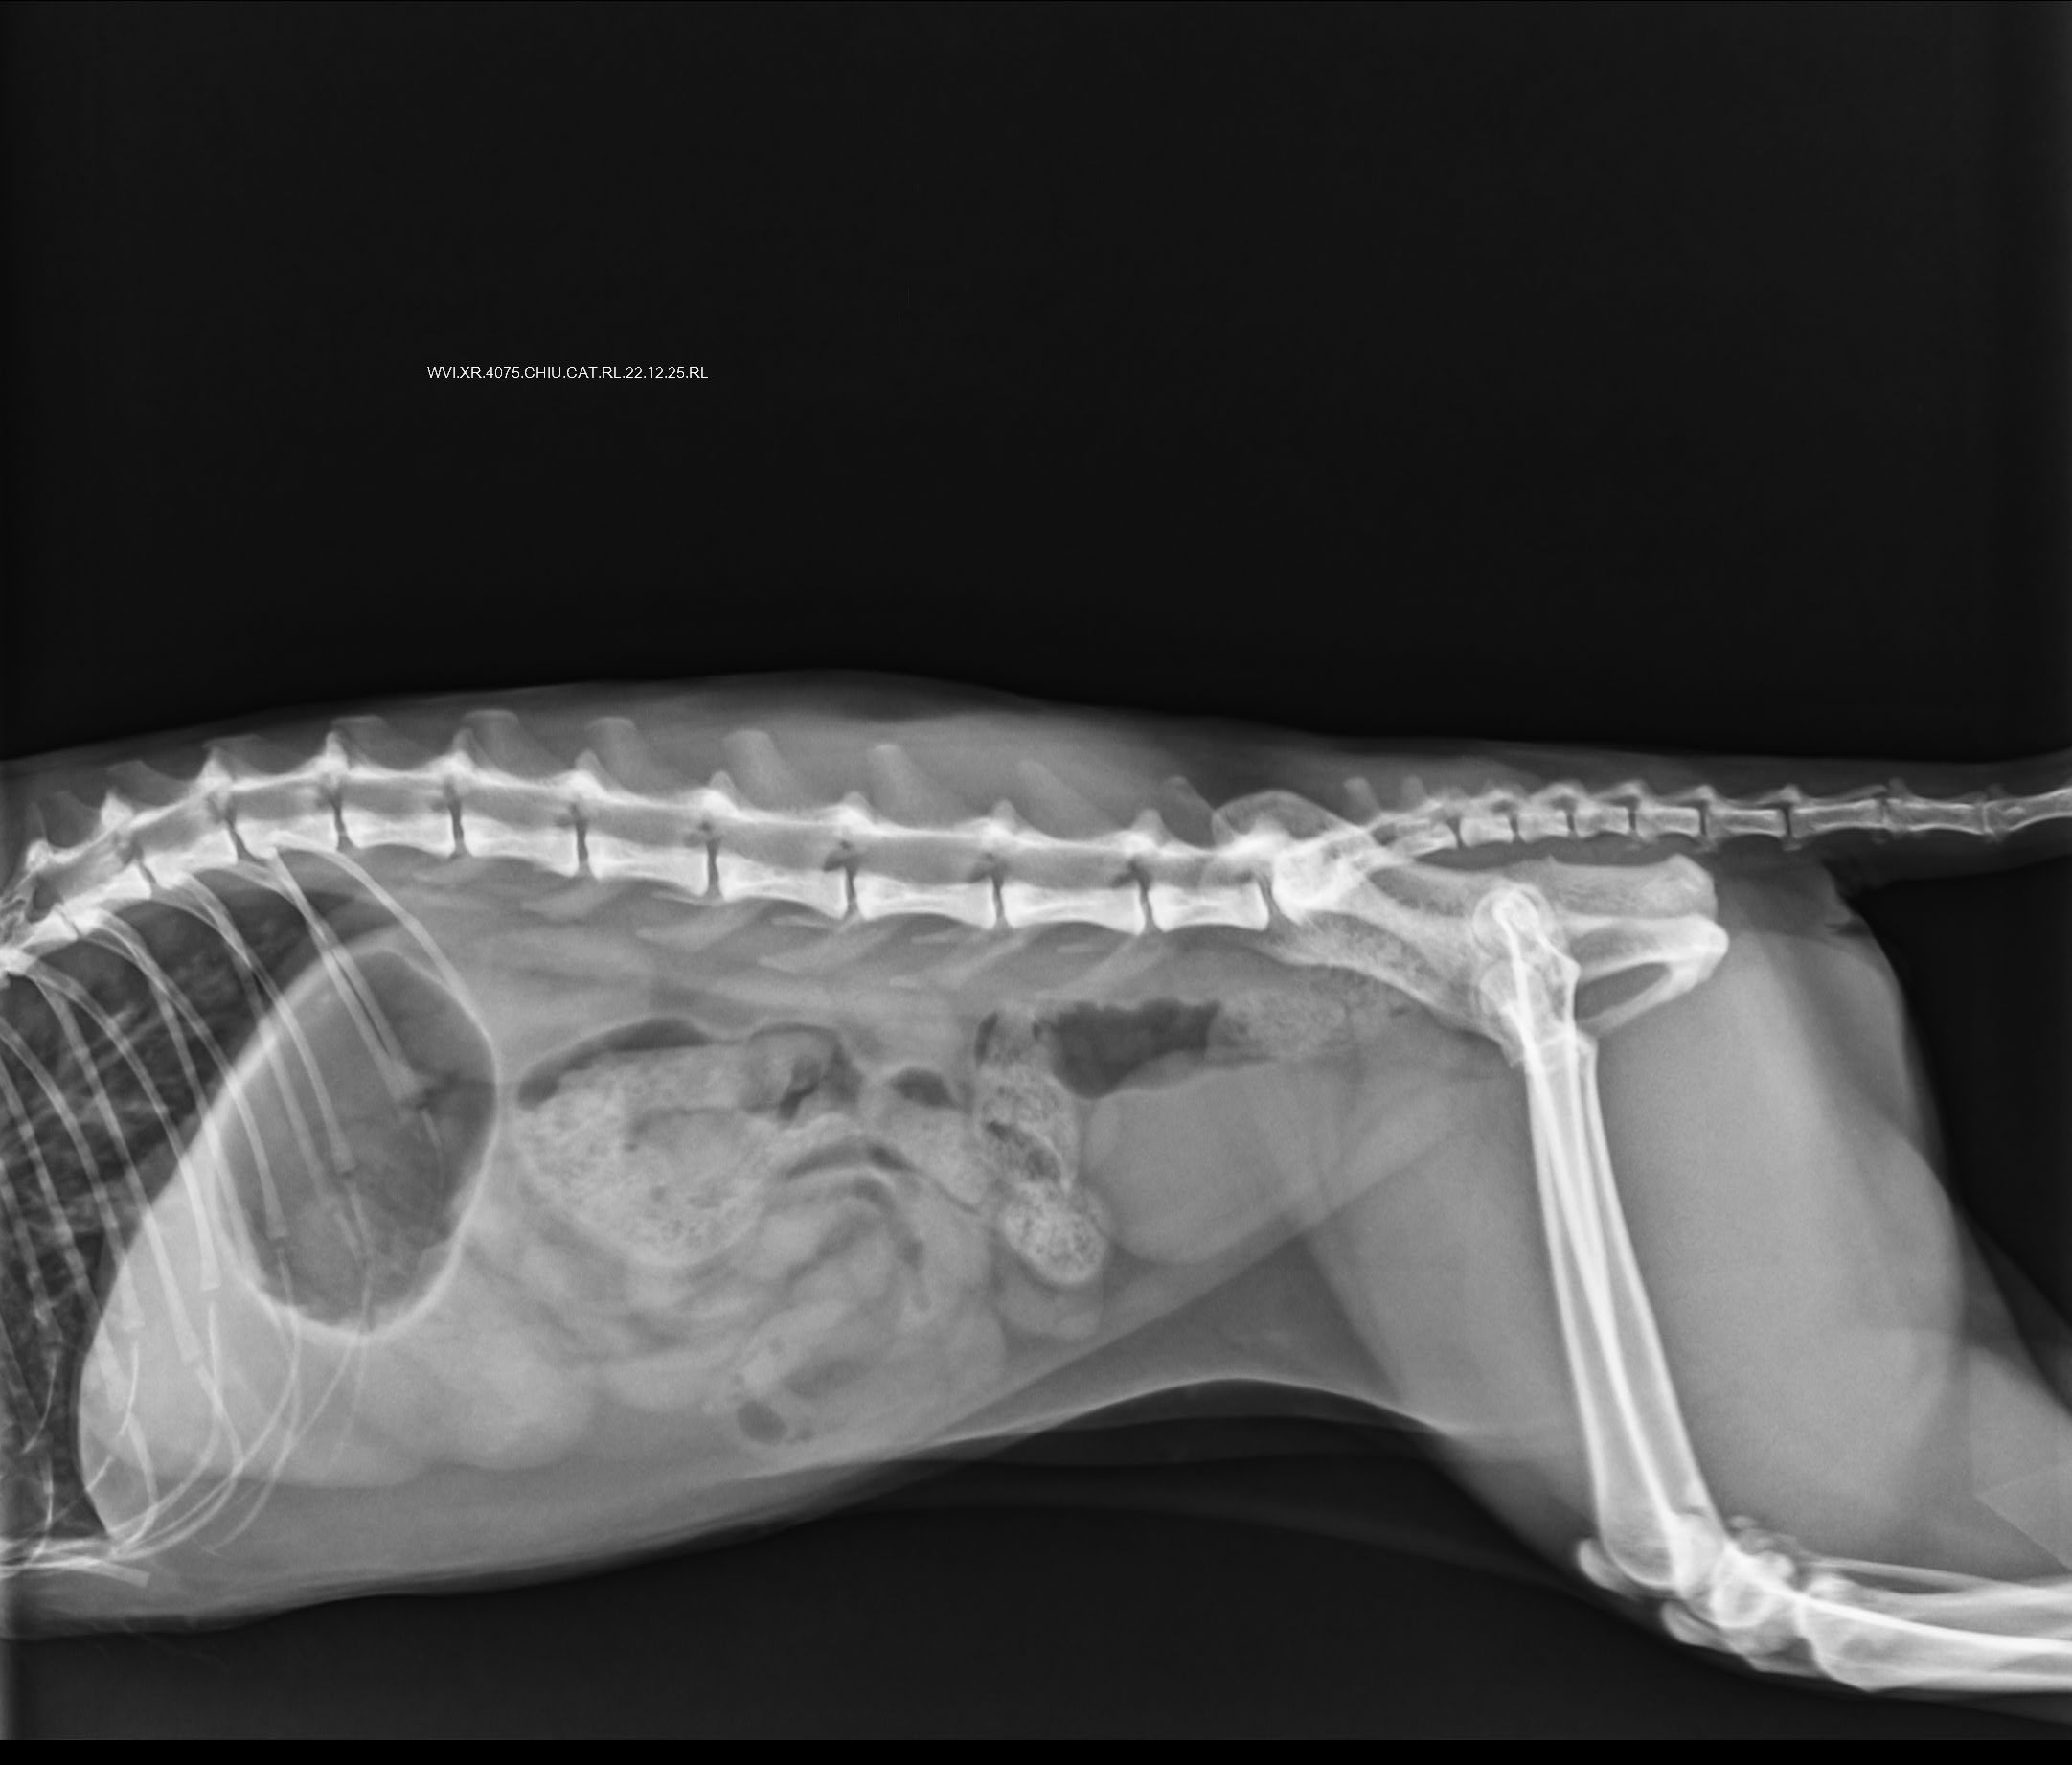

Yesterday was the x-ray which still showed congestion. We did a 2d echo (scans attached). Vet said stuff like HCM, regurgitation, dilation. I had briefly read about HCM and got overwhelmed and didn't ask the vet for more details. But she sent me off with 30 days medicines (long list of meds below) and we'll do a repeat 2d echo after a month. ETA: she lost about 0.5 kg in the last 15 days.

4.1 Xray - RT LAT - Chiu - 20Dec2025.jpeg2.4 MB · Views: 43 -